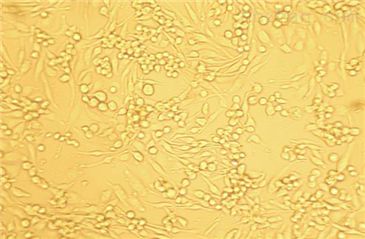

贴壁生长

A-431(表皮癌细胞)全程提供细胞生物体、生长特性、来源、器官、类型、形态、培养条件、应用、组织、冻存条件等复苏及冻存细胞株说明书信息,专业的技术支持您的细胞系实验,让您实验再无烦扰!培养的前一周内出现质量问题,客户可凭细胞的照片以及书面形式的细胞培养,实验操作过程提供给我司。经技术人员核实认定为可以予以重发的情况,由我司再免费提供一次细胞。